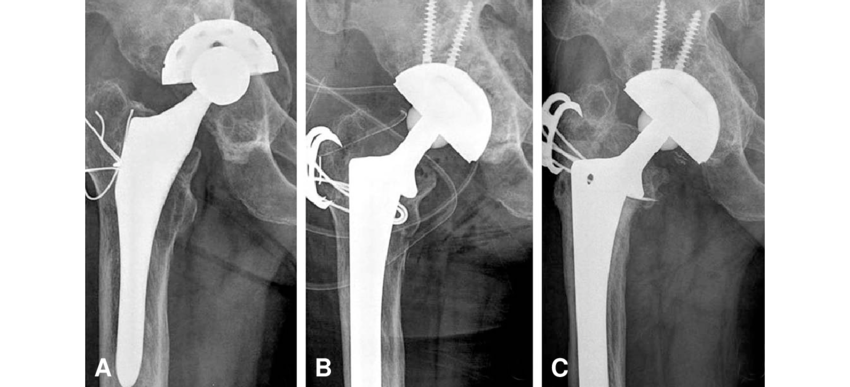

DR.MOHAMMAD HUTAIF, EMIAL Tapered fluted titanium stems are a type of implant used in revision total hip arthroplasty. …

Dr.Mohammad Hutaif, Emial Extensively porous-coated cylindrical uncemented femoral stems are a type of implant used in …